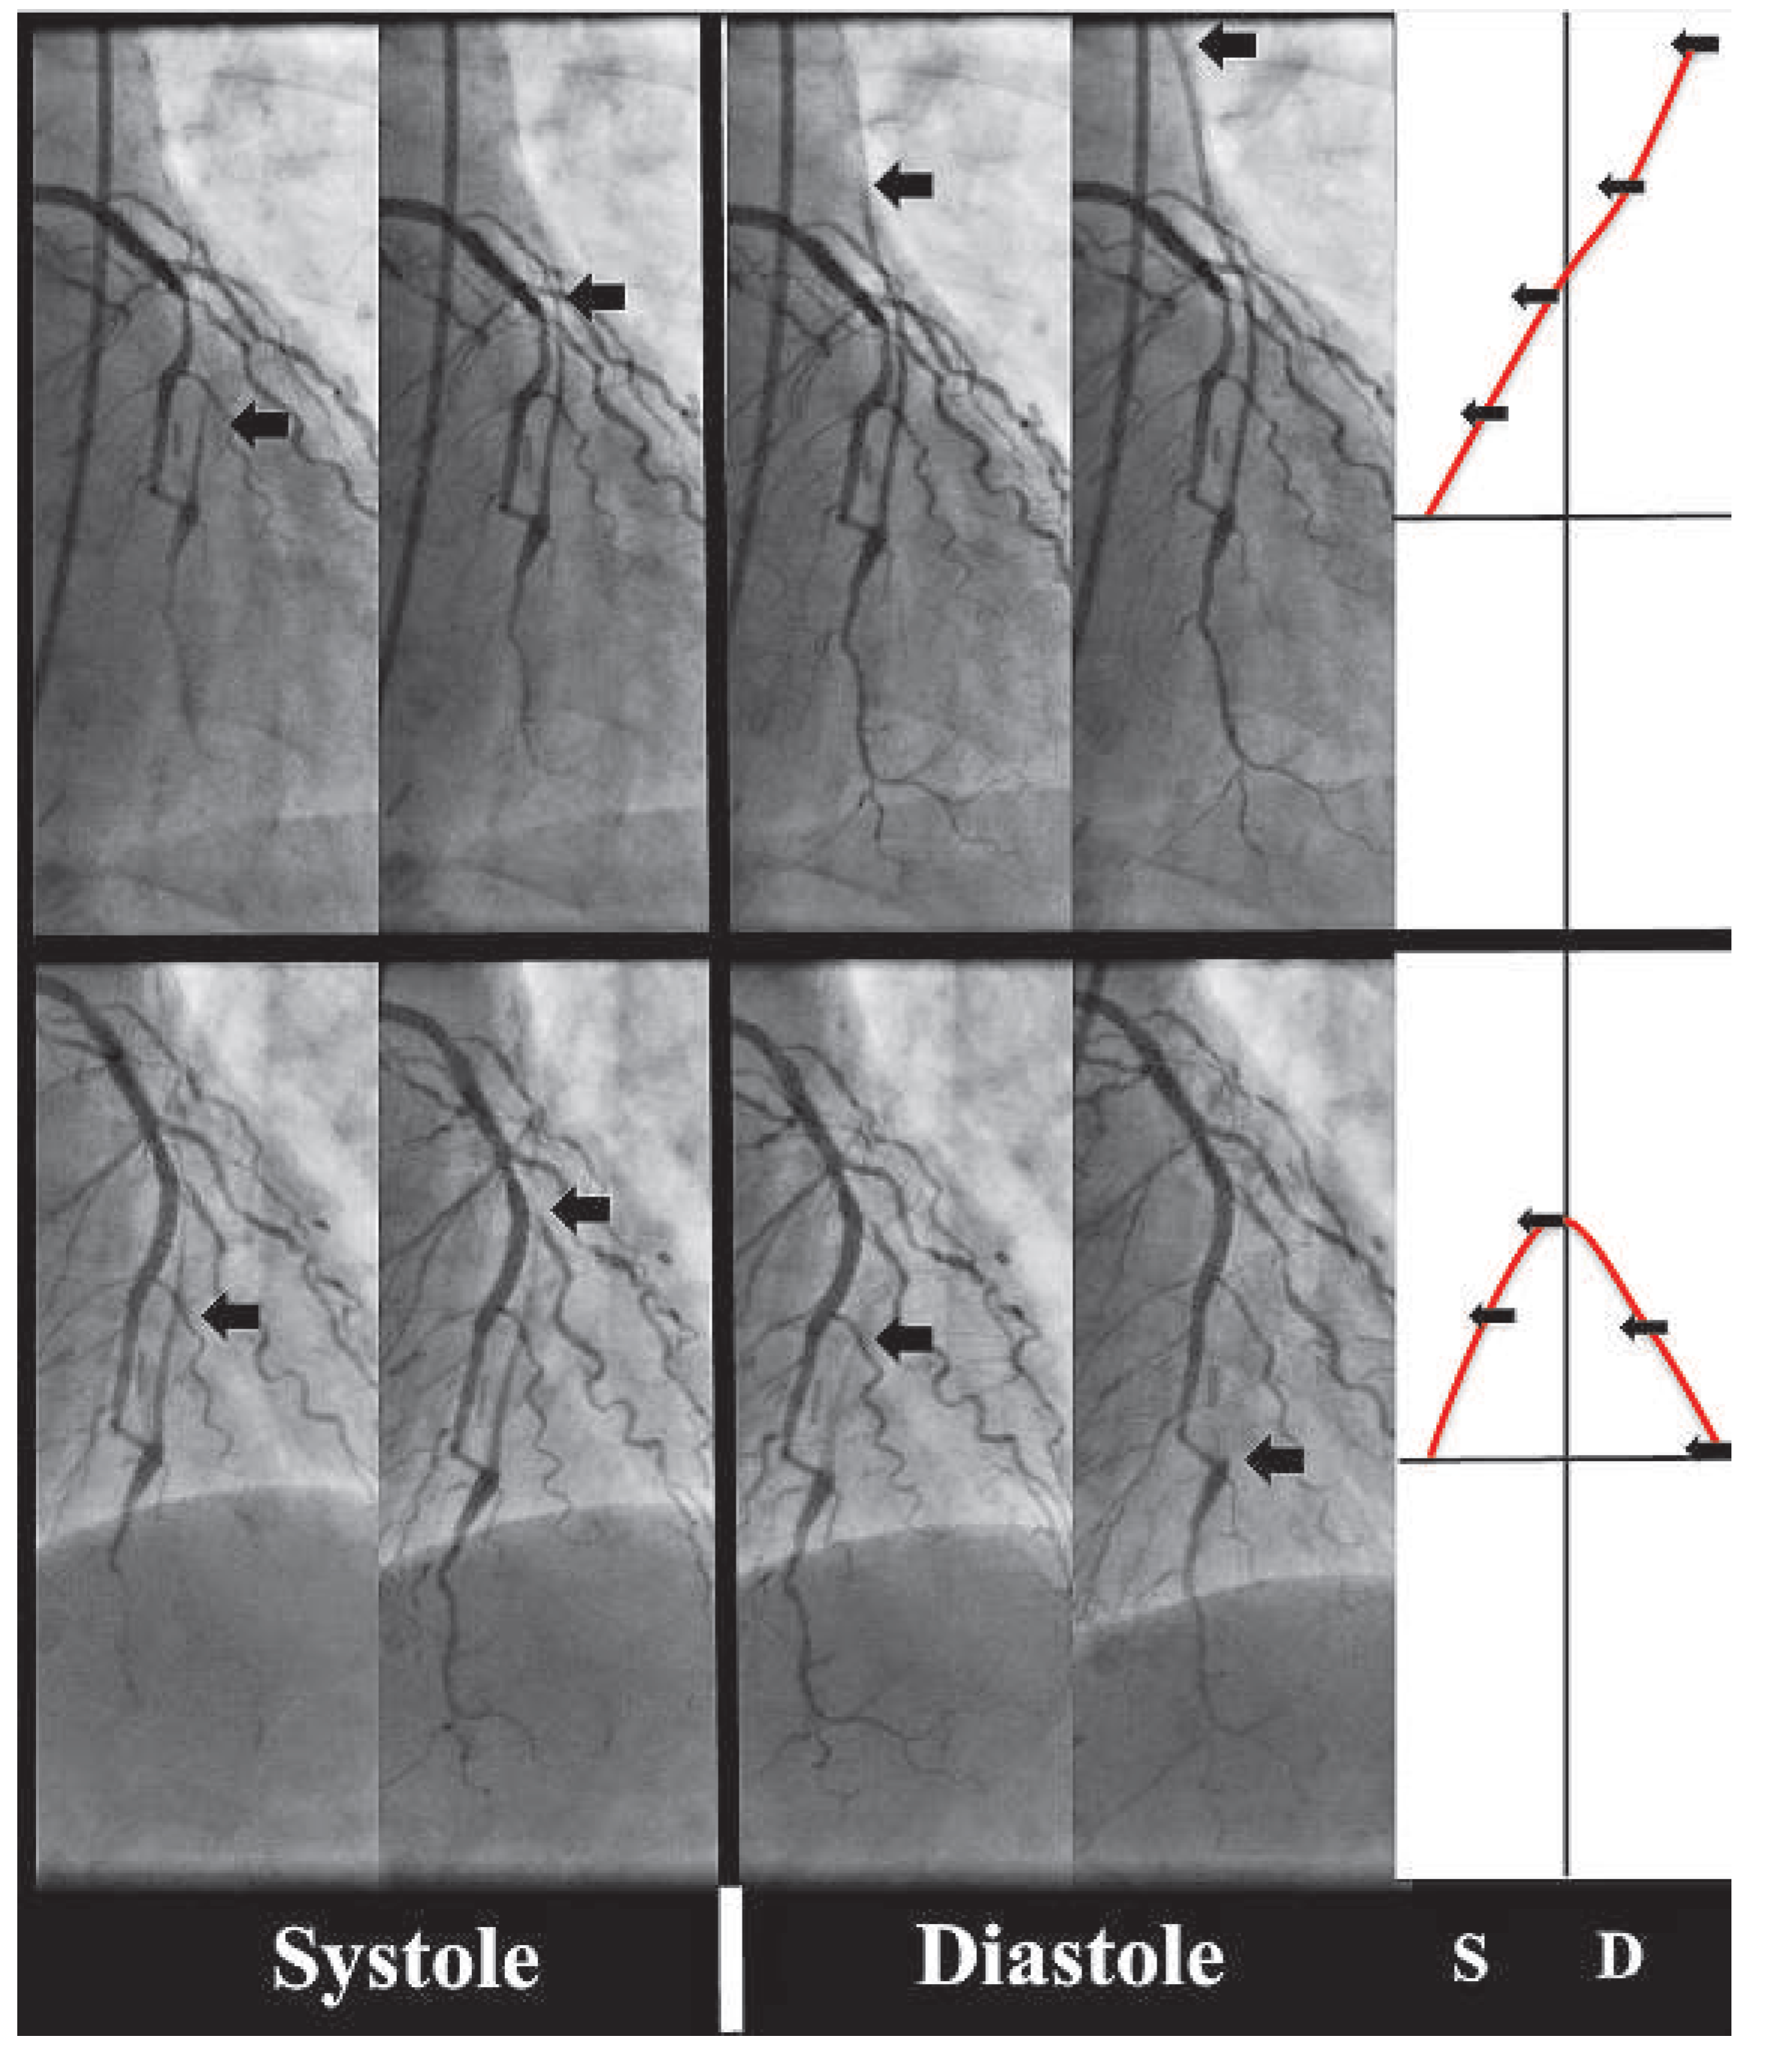

We confirmed the presence of steal due to the ipsilateral AV fistula by occluding the shunt with a pneumatic cuff, which resulted in restoration of antegrade bypass flow during both systole and diastole (Figure 2).

In lack of evidence about the best treatment strategy in this situation, we proceeded to revascularization of the proximal LAD by percutaneous coronary intervention (PCI) and stent implantation, which limited retrograde flow in the graft; a diastolic steal phenomenon was no longer observed (Figure 3 and Figure 4). Nine months later, the patient had not experienced any further anginal symptoms, neither at rest nor during haemodialysis.

Figure 2. Demonstration of ITA steal due to AV shunt using a pneumatic cuff to occlude the fistula. Deflated cuff: selective injection into the left ITA graft shows an opposition to antegrade flow within the ITA graft (A,B), and a prominent wash-out of contrast medium through the subclavian vein in the late phase (B). Inflated cuff: normal antegrade flow in the ITA graft (C,D), and absence of wash-out of contrast medium through the subclavian vein (D). Black arrows indicate the maximum range of antegrade bypass flow. Black stars indicate the subclavian vein.

Figure 3. Demonstration of blood flow in the ITA bypass graft before (upper side) and after (lower side) PCI. The arrows indicate the retrograde extension of contrast media in the bypass graft during injection into the LM coronary artery. Corresponding arrows are represented in the white panel to the right, indicating the extension of contrast media in the ITA (red line) in systole (S) and diastole (D) with respect to the point of anastomosis (black horizontal line).